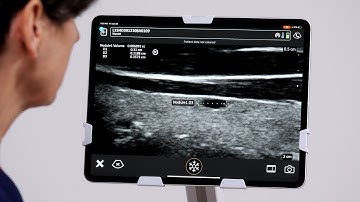

Clarius Feature: TI-RADS Workflow